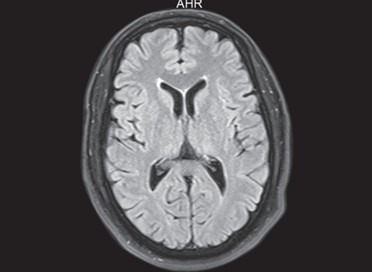

Se pueden mencionar al respecto los estudios que han encontrado en pacientes dependientes al alcohol una disminución del volumen de sustancia gris en el área de la corteza frontal, el hipocampo y el tálamo. El volumen de las sustancias blanca y gris también se puede ver disminuido en el área periventricular, la protuberancia y el cerebelo. Estos déficits de volumen también se han localizado en la corteza prefrontal dorsolateral derecha, ínsula anterior derecha, en el núcleo accumbens y en la amígdala izquierda(16) (ver Imagen 1).

Asimismo, como se indicó previamente, a través de la TC también se puede observar el deterioro de la microestructura cerebral por adicción al alcohol. El abuso de esta sustancia altera cinco fibras del cerebro, como el cuerpo calloso, el fondo de saco, la cápsula externa, el cíngulo circunvolución y el fascículo longitudinal superior, las que están involucradas en funciones como el procesamiento visoespacial y del lenguaje, la comunicación interhemisférica, la memoria, el procesamiento emocional, la toma de decisiones y la integración sensorial(16) (ver Imagen 2).